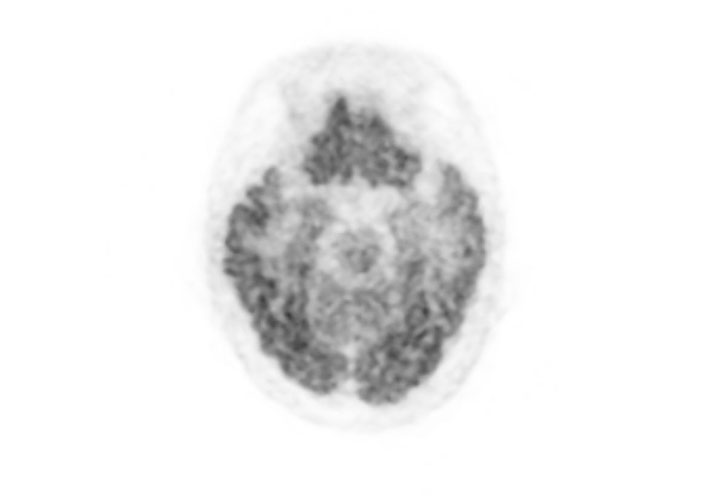

Coronal

- Imaging protocol

- Injected dose: 2.87 MBq/kg, 18F-FDG

- Uptake time: 42 minutes

- Scan time: 30 minutes